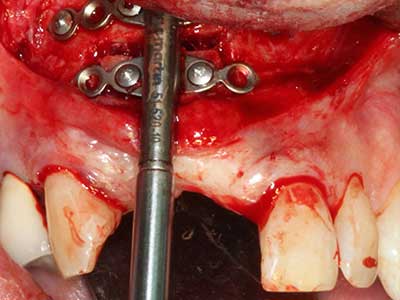

Indication: Preparation near nerves

Indication: Apical resection

When surgical procedures are performed on bone in the immediate vicinity of sensitive structures such as blood vessels or nerves, rotary instruments pose a significant risk of iatrogenic injury. Piezoelectric devices can be helpful for preparation of bone covers and removal of hard tissue close to nerves, particularly for exposure of nerves after iatrogenic injury but also during nerve lateralization for resective and reconstructive procedures or implant placement (Fig. 17-20). Light contact between the piezotip and the nerve does not generally result in damage but proceeding incautiously with saw-like motions or attachments where a residual bone substrate remains may cause temporary or even permanent nerve damage. However, the risk of damage is considered to be substantially lower than when using saws or milling instruments (Pereira, Gealh et al. 2014).